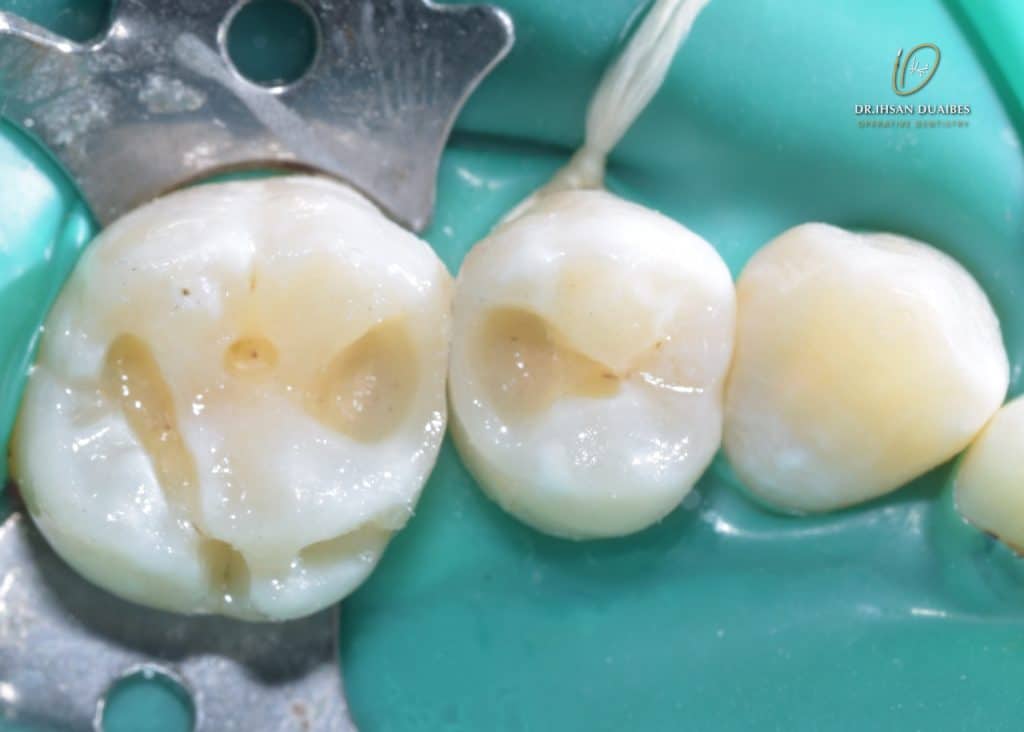

Using split dam ( Because teeth are stick together )

Pulp exposure ( is not bleeding )

Direct pulp caping with MTA ( Map one system facilitate the application ,then bond brush )